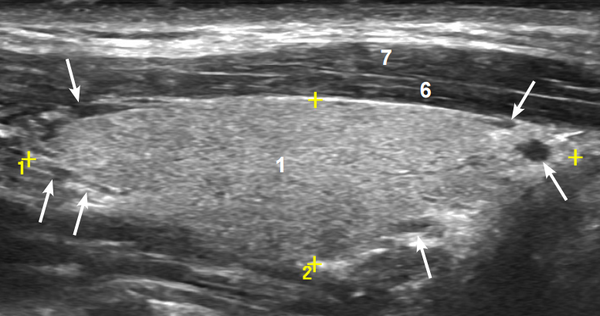

На изображении серая ткань с мелкими вкраплениями — это и есть доля железы. А вот так она выглядит в продольной проекции:

На снимке: 1 — доля щитовидной железы (серая область), 6 — мышцы (тёмные), стрелками указаны сосуды. Жёлтые метки обозначают точки для точного измерения.